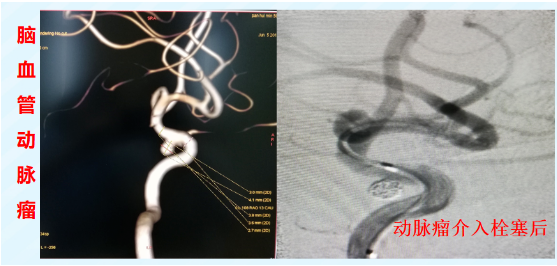

体内的血管就像气球,局部薄弱会膨出形成动脉瘤,一旦破裂大出血,死亡率极高。介入治疗可以经血管送入柔软的弹簧圈或带膜支架,在瘤腔内形成栓塞或覆盖破口,达到“修补”效果,避免了开胸开腹的大手术。

• 神经介入: 急性脑梗死取栓、脑动脉瘤栓塞、脑血管狭窄支架植入。